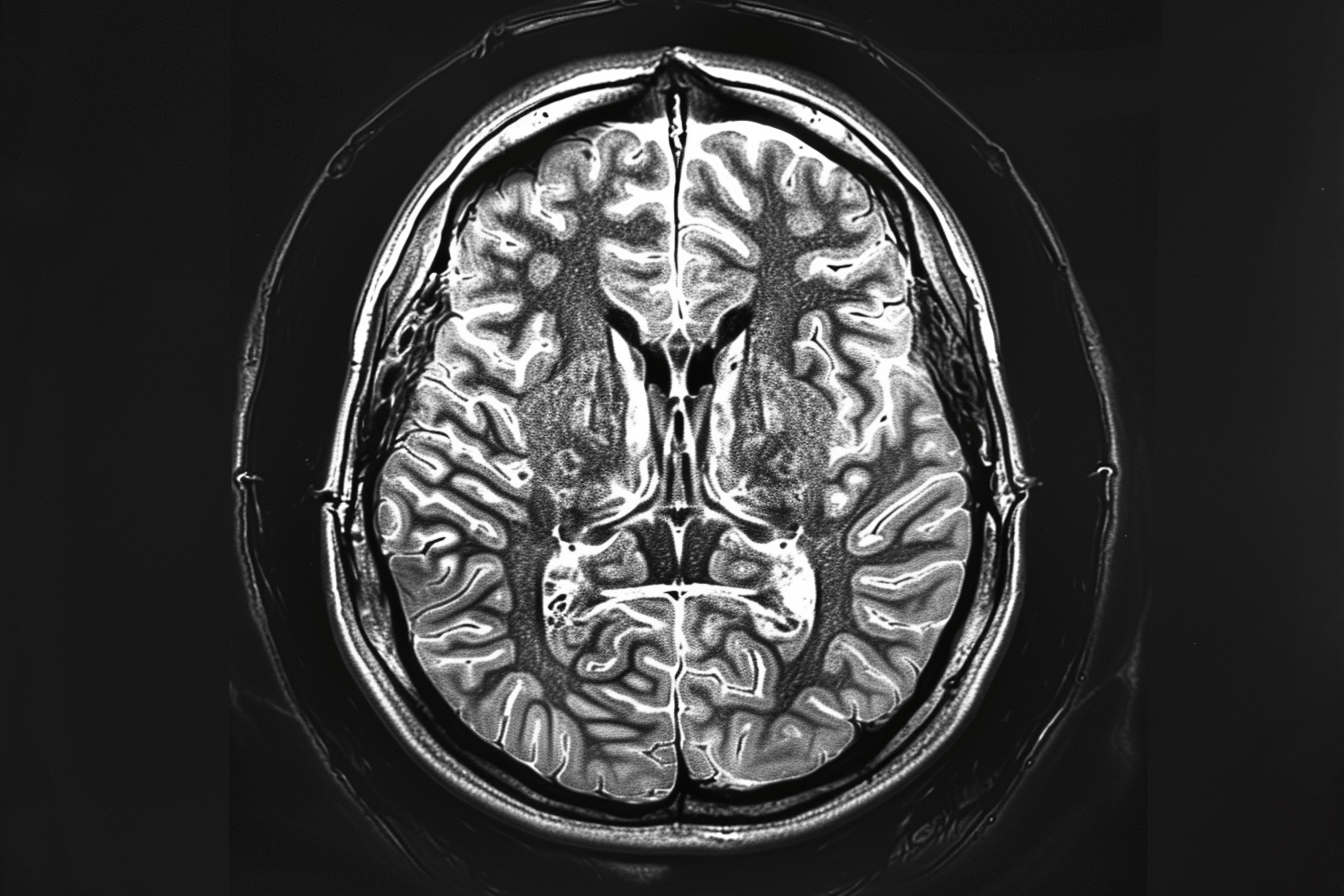

After treatment ends, most patients enter a monitoring phase that relies primarily on MRI scans. MRI is an excellent tool for visualizing structural changes in the brain, such as tumor size, swelling, or shifts in surrounding tissue. However, the fundamental limitation is that MRI does not detect early biological activity.

In the months following treatment, tumor cells may already be active at a microscopic level. These cells can begin dividing, altering local metabolism, and interacting with surrounding brain tissue. Yet none of these early processes are visible on standard MRI. By the time MRI shows a clear abnormality, the disease has often progressed beyond its earliest stage [9].

In the first few months after surgery, radiation, and chemotherapy, most patients enter what appears to be a stable phase. MRI scans may show no visible tumor, and symptoms may temporarily improve. This period often creates a sense of relief.

However, at a microscopic level, residual tumor cells are still present. These cells may remain inactive or begin slow regrowth during this time. Clinical data shows that even after aggressive treatment, complete eradication is rare, and the disease often persists in a hidden form [1].